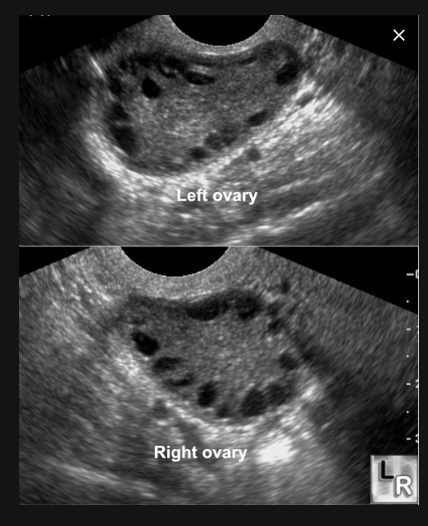

What would you see of pelvic USS that is a diagnostic indicator of PCOS

12 or more peripheral antral follicles or increased ovarian volume >10cm3